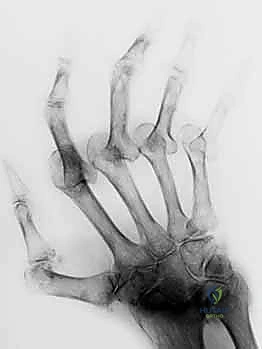

على عكس تشوه العروة تماماً، يتميز تشوه عنق البجعة بفرط استقامة (Hyperextension) في المفصل الأوسط (PIP) مع انثناء (Flexion) في المفصل الأخير (DIP). هذا الشكل المتعرج يشبه بالفعل الانحناء الرشيق لعنق طائر البجعة، ولكنه وظيفياً يمثل إعاقة كبيرة لليد، حيث يفقد المريض القدرة على إغلاق قبضة يده بشكل صحيح.

الأسباب المؤدية لتشوه عنق البجعة

- التهاب المفاصل الروماتويدي: هو السبب الأكثر شيوعاً. الالتهاب يؤدي إلى ارتخاء وتمدد "الصفيحة الراحية" (Volar Plate) - وهي رباط قوي يمنع المفصل الأوسط من الانحناء للخلف أكثر من اللازم.

- إصابات الصفيحة الراحية (Volar Plate Injuries): نتيجة التواء شديد للإصبع للخلف.

- إصابات إصبع المطرقة (Mallet Finger) غير المعالجة: إذا تمزق الوتر الباسط عند المفصل الأخير ولم يُعالج، فإن الخلل الميكانيكي ينتقل تدريجياً للمفصل الأوسط مسبباً فرط استقامته.

- الشد التشنجي (Spasticity): في حالات الشلل الدماغي أو السكتات الدماغية، حيث تنقبض العضلات بشكل غير طبيعي.

الأعراض والمضاعفات

- صعوبة بالغة في ثني الإصبع لعمل قبضة (إمساك الأشياء يصبح شبه مستحيل في الحالات المتقدمة).

- ألم في قاعدة الإصبع والمفاصل المتأثرة.

- طقطقة أو "تعليق" الإصبع عند محاولة ثنيه (Snapping).